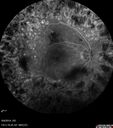

Vitreous Hemorrhage - Full PRP - FA no NV

57 year old female Type 1 DM with prior laser about 10 years ago in Chicago.

HTN, Thyroid cancer and removal, Cardiovascular disease

Meds: ASA 325 mg /day, etc

Recent new floaters in the right eye:

VA 20/50 OD, 20/40 OS